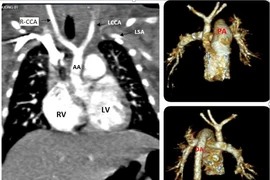

(khoahocdoisong.vn) - Gián đoạn quai động mạch chủ là một dị tật tim bẩm sinh cần được phát hiện sớm và phẫu thuật kịp thời nếu không bệnh dễ gây tử vong cho trẻ.

Kỹ thuật đặt stent graft được coi là một bước đột phá của nền y học hiện đại, giúp đem lại những hiệu quả vượt trội so với các phương pháp phẫu thuật truyền thống để điều trị bệnh lý động mạch chủ.

Lóc tách động mạch chủ type A cấp tính là một thảm họa thực sự của bệnh tim mạch. Khoảng 50% bệnh nhân tử vong trong 48 giờ đầu, 60% trong tuần đầu. Khi đã vỡ, gây ép tim cấp, tỷ lệ tử vong gần như 100%.

(khoahocdoisong.vn) - 70 – 80% lóc tách động mạch chủ (ĐMC) tử vong trong 2 tuần đầu. Có nhiều nguy cơ gây bệnh nhưng tăng huyết áp và tuổi là yếu tố thường gặp nhất.